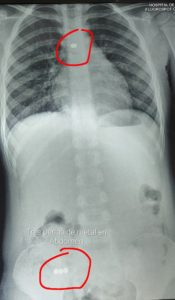

Un llamado de atención para todos los padres: a través de sus redes sociales, el Dr. Carlos Morínigo, especialista en Neumología, dio a conocer el caso de una niña de tan solo 4 años, que sufrió un grave cuadro de salud luego de tragar un collar de perlas de metal.

Según detalló el médico, la pequeña fue llevada primeramente al Hospital de Trauma y luego al Ineram, 48 horas después de haber introducido el collar en la boca. Por desgracia, el collar se soltó y liberó las perlas: cuatro se alojaron en el aparato digestivo y una en el pulmón, causando una neumonía grave bilateral.

Al ingresar al centro de alto complejidad, la paciente fue examinada por el Dr. Morínigo, quien manifestó que observó pus en todos los bronquios y, en el fondo de la base del pulmón, una perla alojada.

Afortunadamente, el equipo médico logró extraer con sumo cuidado la perla alojada en el pulmón. Luego, volvió a intubar a la niña y derivarla a terapia intensiva para el tratamiento de la neumonía grave.